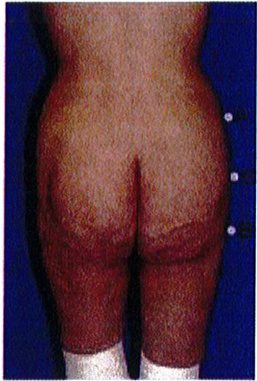

Hình chữ V (Hình quả táo)

Khoảng 15% số bệnh nhân có dạng khung hình chữ V. Khi nối điểm A và B với nhau, có thể thấy chúng hội tụ lại 1 điểm ở dưới mông, tạo hình chữ V. Hầu hết mô mỡ nằm ở vùng mặt ngoài hông (điểm A) và rất ít ở điểm B. Ở dạng này, tình trạng lõm ở điểm C không quá đáng ngại. Khi điểm A nhỏ đi, mông sẽ có khung vuông.

CƠ MÔNG LỚN

Dạng khung mông hình chữ V là dạng khó chỉnh hình nhất. Hình dạng chữ V này không hấp dẫn người nhìn cho lắm, nên có thể cải thiện bằng cách hút mỡ ở điểm A và vùng mạn sườn. Đồng thời cũng cần ghép mô mỡ vào vùng mặt ngoài đùi trên để cải thiện hình dạng chữ V này (Hình 15) trong những trường hợp khó. Ngoài ra nếu điểm C có vùng lõm quá rõ ràng thì cũng nên ghép mô mỡ thêm vào để cải thiện tính thẩm mỹ của khu vực.

Hình. 15. Khung hình chữ V, cao với khối cơ mông lớn ngắn trước (trái) và sau (phải) phẫu thuật tạo hình.